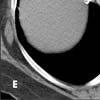

A CT image below the level of the heart (E) shows extensive venous collaterals that extend to the inferior vena cava (arrows). Venous collaterals extending to the inferior vena cava are also evident on another slice in the upper abdomen (F, arrows).

The lesion in the right supraclavicular region is visible on the superior aspect of the study (G, arrow). Images in lung windows, surprisingly, are unrevealing, as are images of the more cephalad aspects of the neck.